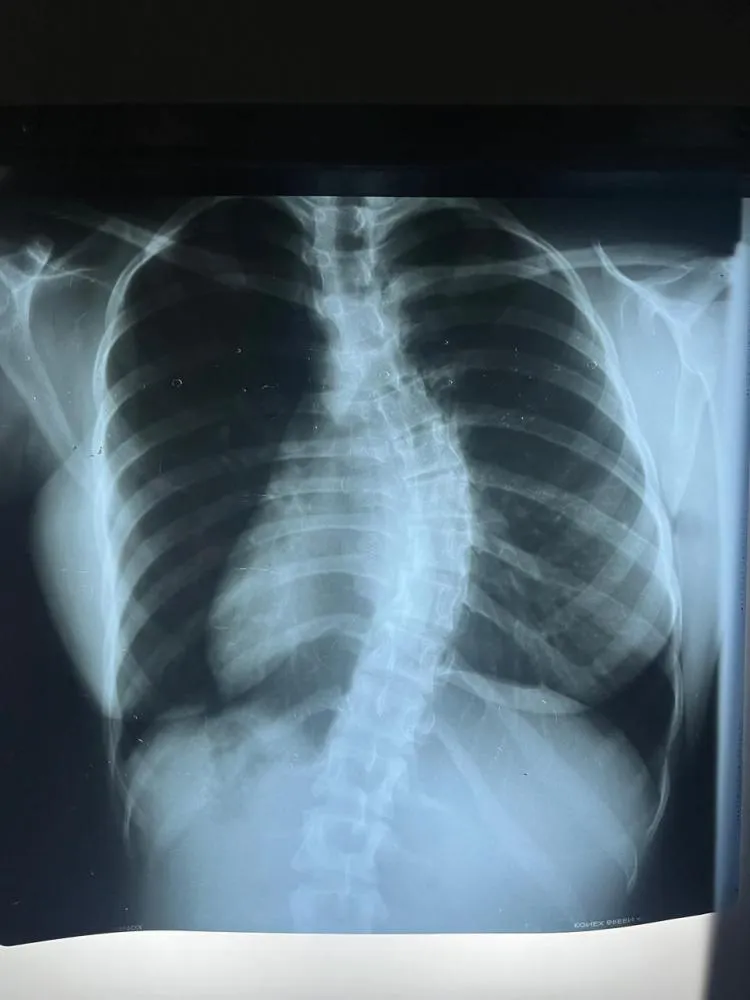

A paciente, diagnosticada com uma escoliose classificada como Lenke 1 e progressiva, necessitava de intervenção cirúrgica urgente devido à evolução da curvatura e ao impacto na sua qualidade de vida. A cirurgia visou corrigir a deformidade, utilizando implantes e instrumentação para alinhar a coluna vertebral e proporcionar maior estabilidade. De acordo com os especialistas, o procedimento incluiu monitorização neurofisiológica, garantindo a preservação das funções neurológicas durante toda a operação.

Estima-se que, no Brasil, cerca de 2% a 4% da população desenvolvam escoliose, sendo mais comum em adolescentes do sexo feminino. Nos casos em que a curvatura ultrapassa os 40º, como ocorreu nesta paciente, a cirurgia passa a ser indicada, especialmente quando tratamentos conservadores, como fisioterapia e o uso de coletes, não apresentam resultados satisfatórios.